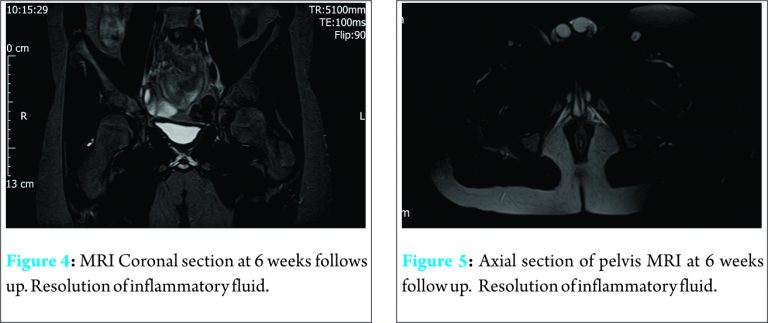

At 2 weeks, his hip pain had fully resolved, and he demonstrated a full range of painless active hip movement, although he continued to use crutches when walking. There was no tenderness over the gluteal or trochanteric region. At 4 weeks, he was permitted full weight bearing without any support. His CRP was < 3 mg/L. A repeat MRI scan at 6 weeks showed no evidence of any oedema or fluid collection in and around right gluteus musculature ( Figs 4 and 5).